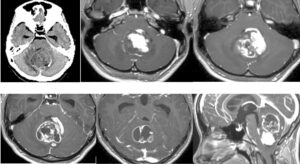

視力障害、記銘力障害で発症した頭蓋咽頭腫を両側前頭開頭、anterior interhemispheric approachで切除しました。トルコ鞍部や鞍上部にはほとんど局在しないためtranslamina-terminalis approachを選択しました。視床下部動脈を温存し、内減圧を繰り返し、焼き鳥テクニックとリングキュレットで狭い術野から腫瘍を起こして摘出しました。術後年齢が比較的若かったためかすぐに覚醒しました。

両側前頭開頭でSSS前端を結紮切断。Orbitaは外さず。